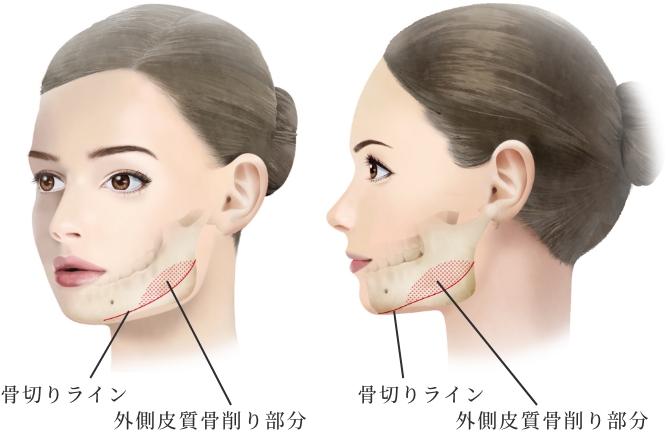

小木曽クリニックの

『頬骨形成骨切り術』の特徴

頬骨体部から弓(アーチ)

部に至る広範囲な骨切りが

可能

骨切り部位は頬骨弓部から体部前面に至り、L字型に長く幅広く切除し頬骨全体を内下方へ移動するため、頬骨全体に縮小効果があります。L字型に合計4回の骨切りが必要なため、複雑で精密な手技が必要な施術です。